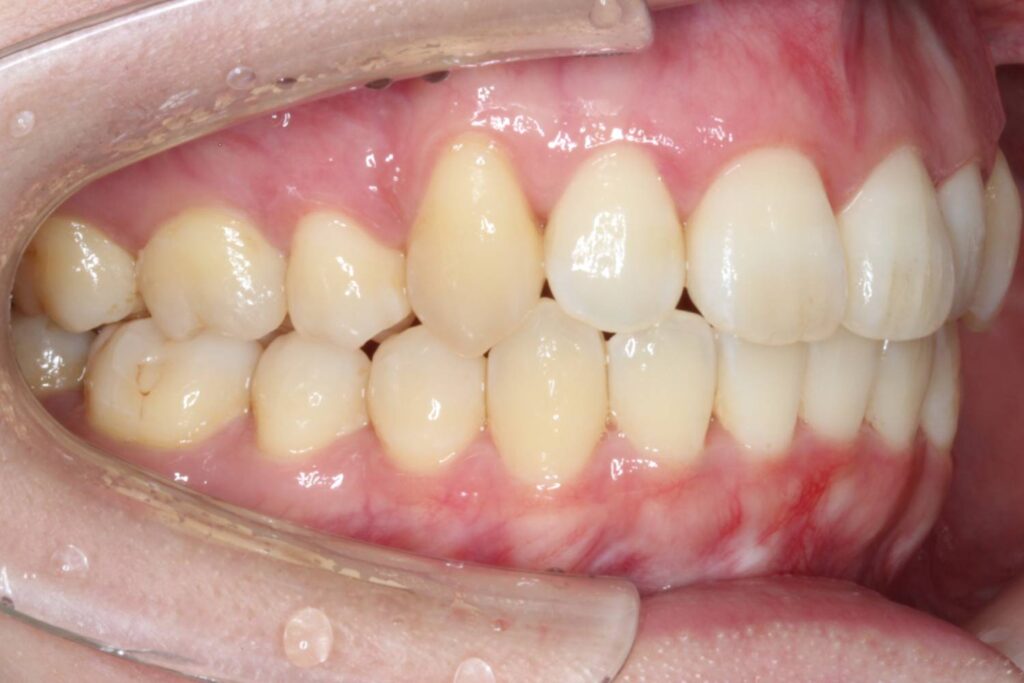

前歯に叢生があり、特に右上の前歯は前方に突出していて目立ってしまっています。

また、上顎の犬歯は「八重歯」と呼ばれる状態で、唇をよく噛んでしまったり、口内炎ができてしまうとのことでした。

奥歯の噛み合わせは、下顎に対して上顎が前方にずれてしまっています。

Before